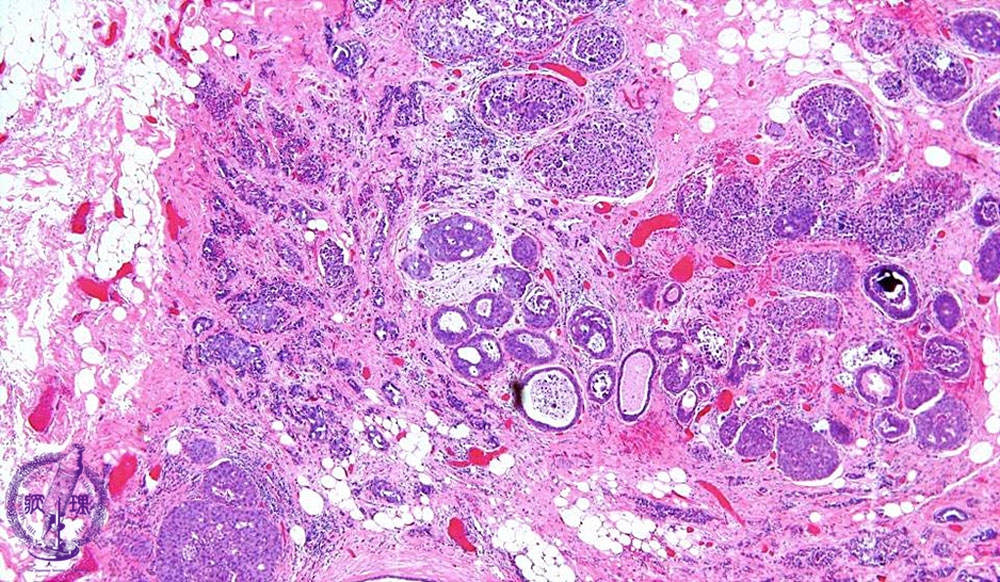

- 14.Breast

- ★(6)Invasive ductal carcinoma(Papillotubular carcinoma)

Microscopic image(HE stain, low power view):An example of well-differentiated type of invasive ductal carcinoma showing duct formation and/or papillary proliferation. In addition to intraductal spread, extensive stromal invasion (dotted line) is also apparent.